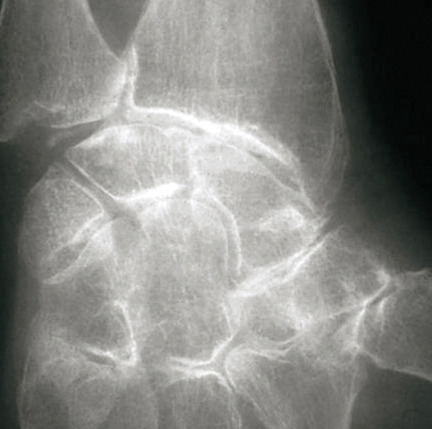

La forme pseudorhumatoïde est rare (5 %), simulant une polyarthrite rhumatoïde. L’arthrite chronique à PPC se présente comme une oligo- ou une polyarthrite, avec parfois des signes systémiques d’inflammation (élévation de la vitesse de sédimentation et de la protéine C-réactive [CRP]). La superposition d’accès aigus microcristallins est évocatrice de ce diagnostic. Il s’agit d’un diagnostic différentiel de polyarthrite rhumatoïde du sujet âgé ou de pseudopolyarthrite rhizomélique. Le diagnostic repose sur la mise en évidence des cristaux de PPC, même si les radiographies standard sont évocatrices. L’atteinte radiographique associe des calcifications des cartilages articulaires (fig. 7) et des fibrocartilages (fig. 8, 9, 10 et 11) [à rechercher systématiquement sur les radiographies de poignets, genoux et symphyse pubienne]. La mise en évidence d’une chondrocalcinose sur des radiographies standard renforce le diagnostic de rhumatisme à PPC mais l’absence de dépôts calciques ne l’élimine pas (la sensibilité de la radiographie standard étant imparfaite). L’échographie peut mettre en évidence des dépôts de PPC, qui apparaissent comme une fine bande hyperéchogène au sein des cartilages hyalins et comme des points scintillants dans les fibrocartilages ou dans la membrane synoviale. La sensibilité de l’échographie est bien supérieure à celle de la radiographie standard. Le scanner peut également mettre en évidence des dépôts calciques évocateurs, notamment au niveau du rachis ou du bassin qui sont plus difficilement explorés par les radiographies et l’échographie.